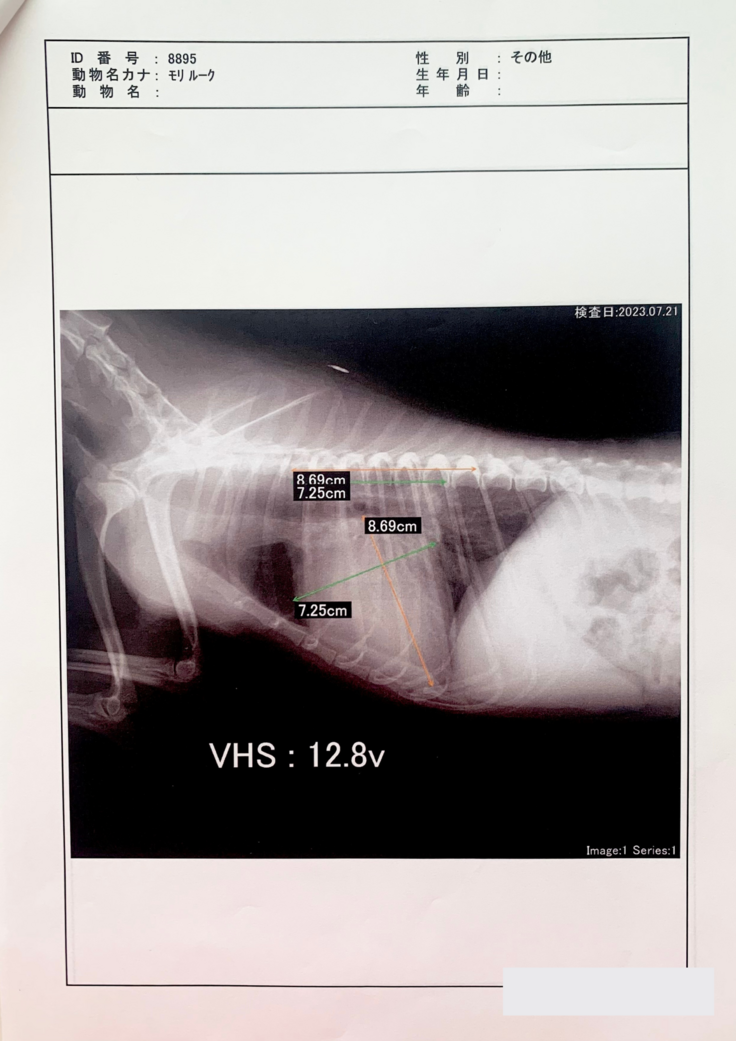

僧帽弁閉鎖不全症

度々の咳が続き、気になり検査したところ、2023年の1月に、「僧帽弁閉鎖不全症」という病気だったということが分かりました。

僧帽弁とは、左側の左心房と左心室の間にある弁のことです。通僧帽弁の働きにより左心房から左心室への一方向にしか血液は流れませんが、僧帽弁閉鎖不全症では、弁がうまく閉まらなくなることで逆方向の血流が認められるようになります。心臓が大きくなると、心臓だけでなく肺にも血液が溜まり、肺水腫と呼ばれる状態になります。

手術でしか治るものはなく、それをしなければ薬で延命治療をするというものです。

その後2月、4月、7月に病院に行っています。

最終的に肺水腫と気管虚脱も発症しており、

かなりの重症でした。